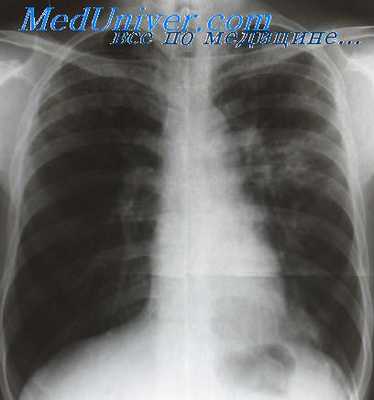

Рентгенологически в начальной фазе фибринозного плеврита определяется малоинтенсивное затемнение главным образом в нижнем отделе легочного поля за счет скопления экссудата над диафрагмой. Следует подчеркнуть, что при исследовании больного в вертикальном и горизонтальном положении на спине обнаружение жидкости затрудняется. Оно становится более доступным при латероскопии и латерографии.

После выпадения фибрина отмечается диффузное понижение прозрачности нижне-наружных отделов легочного поля. При образовании плевродиафрагмальных сращений отмечается симптом Вильямса — отставание подвижности купола диафрагмы на больной стороне при глубоком вдохе. Вместе с тем изменяются нормальные контуры диафрагмы: они приобретают нерезкое очертание с многочисленными и неравномерными зубцами, обращенными вверх. При этом наружный и задний реберно-диафрагмальные синусы не расправляются при вдохе. При небольших плеврокостальных фибринозных наслоениях отмечается усиление сосудисто- и соединительнотканного рисунка легкого, что зависит от влияния добавочного поглощающего рентгеновские лучи слоя этих наслоений и мало интенсивных интерстициальных изменений в междольковых перегородках.

- Иная картина типична для экссудативного туберкулезного плеврита. Физикальное обследование выявляет сглаженность (при большом объеме экссудата – выбухание) межреберий, притупление перкуторного звука над областью скопления экссудата, смещение структур средостения в здоровую сторону. В острой фазе изменения гемограммы характеризуются значительным лейкоцитозом и ускорением СОЭ, лимфо- и эозинопенией. При рентгенологическом и ультразвуковом исследовании определяется свободная жидкость в полости плевры. Детальная оценка состояния легочной ткани возможна только после эвакуации экссудата. Диагноз гнойного плеврита подтверждается при получении гнойного экссудата во время плевральной пункции.